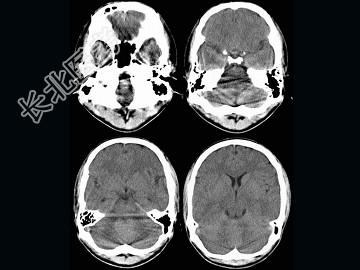

- 单项选择题男,16岁, 头痛、呕吐10天,CT检查, 最可能的诊断为 ( )

A、脑膜瘤

B、髓母细胞瘤

C、室管膜瘤

D、脑血管瘤

E、血管母细胞瘤